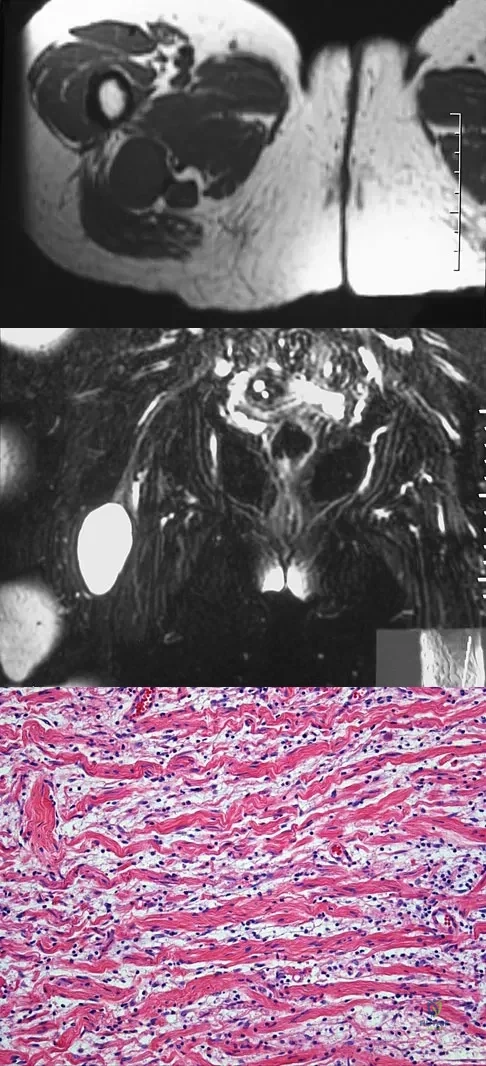

A 54-year-old woman reports worsening pain in her buttock, especially when sitting for long periods of time. She has occasional pain and paresthesias radiating down her posterior leg. She has no significant medical history. MRI scans are shown in Figures 15a and 15b and a biopsy specimen is shown in Figure 15c. What is the most likely diagnosis?

Explanation

A 38-year-old man has an enlarging left paraspinal soft-tissue mass. Based on the MRI scans and biopsy specimens shown in Figures 32a through 32e, what is the most likely diagnosis?

Explanation